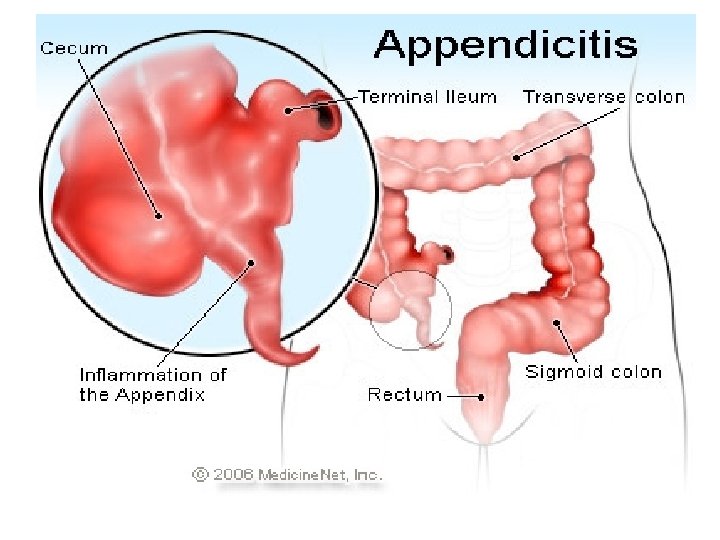

Apendisiti akut eshte inflamacioni i appendiksit, eshte nje nder shkaqet e abdomenit akut dhe gati 60% e urgjencave abdominale.

• Inflamacioni i apendiksit ndodh pas bllokimit te pjesshem/te plote te lumenit te apendiksit nga masa fekaloide, masa parazitare, trupa te huaj, tm.

• Kanali i bllokuar zgjerohet, tendoset, krijohet staze e qarkullimit te linfes, iskemi, mikroinfarkte deri ne gangrene te apendiksit. • Ketu ndodh edhe invadimi bakterial i hapesires apendikulare dhe inflamacioni I cili zhvillohet shtrese pas shtrese me hiperemi e deri ne infiltrim purulent.

KLINIKA: • DHIMBJA: Fillimisht e moderuar ne forme kolike ne regionin periumbilikal, me pas shnderrohet ne dhimbje te qendrueshme e zhvendosur ne kuadrantin inferior dexter.

NE PALPIM: - Mac Burney (+): 1/3 e poshtme e distances prej umbilikusit ne spina iliake anteriosuperior

- Rebound (+): dhimbja e madhe gjate heqjes se menjehershme te dores palpuese ne kuadrantin inferior dexter. - Defans (+): mbrojtje muskulare ne kuadrantin inferior dexter. - Temperature: subfebrile- e larte, e shoqeruar me frisone +/- te vjella - Leukocitoze - Crregullime te tranzitit: konstipacion, rralle diare.